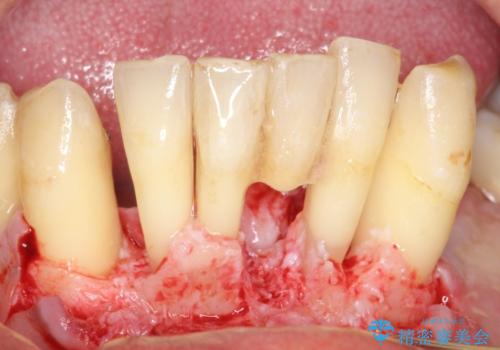

精査したところ、全顎的な重度の歯周病により下顎前歯に激しい動揺を認めました。

できるだけ自分の歯を残したいという患者様の強いご希望により、禁煙指導後再生療法(骨を増やす手術))を行いました。

再生療法から1年後リエントリー手術により骨の再生を確認し、骨外科処置(骨を平らにして歯周ポケットの根本的な改善を図る処置)を行ったのち、連結補綴を行いました。